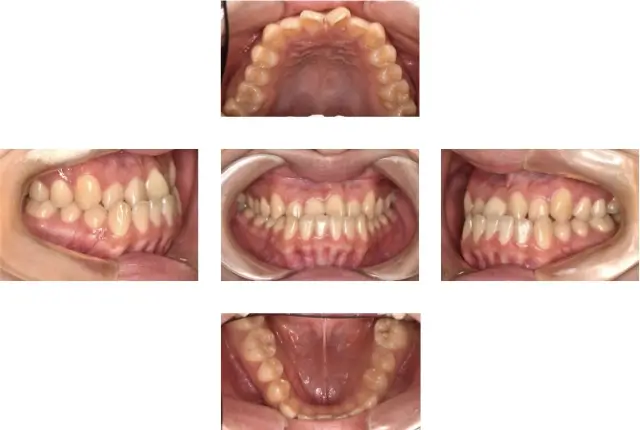

受け口(下顎前突)治療 1

初診時年齢 11歳5ヶ月 主訴 受け口が気になる

診断名 下顎前突 治療に用いた主な装置 マルチブラケット装置

抜歯の有無 非抜歯 治療期間/回数 2年1ヶ月/22回

費用の総額 1,056,000円(税込) 費用内訳

初診時年齢 11歳5ヶ月

主訴 受け口が気になる

診断名 下顎前突

治療に用いた主な装置 マルチブラケット装置

抜歯の有無 非抜歯

治療期間/回数 2年1ヶ月/22回

費用の総額 1,056,000円(税込)